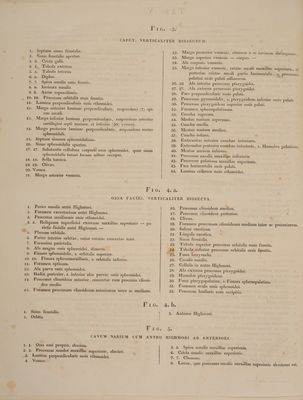

Icones anatomicae / [Conrad Johann Martin Langenbeck].

- Konrad Johann Martin Langenbeck

- Date:

- 1826-1841]

Credit: Icones anatomicae / [Conrad Johann Martin Langenbeck]. Source: Wellcome Collection.